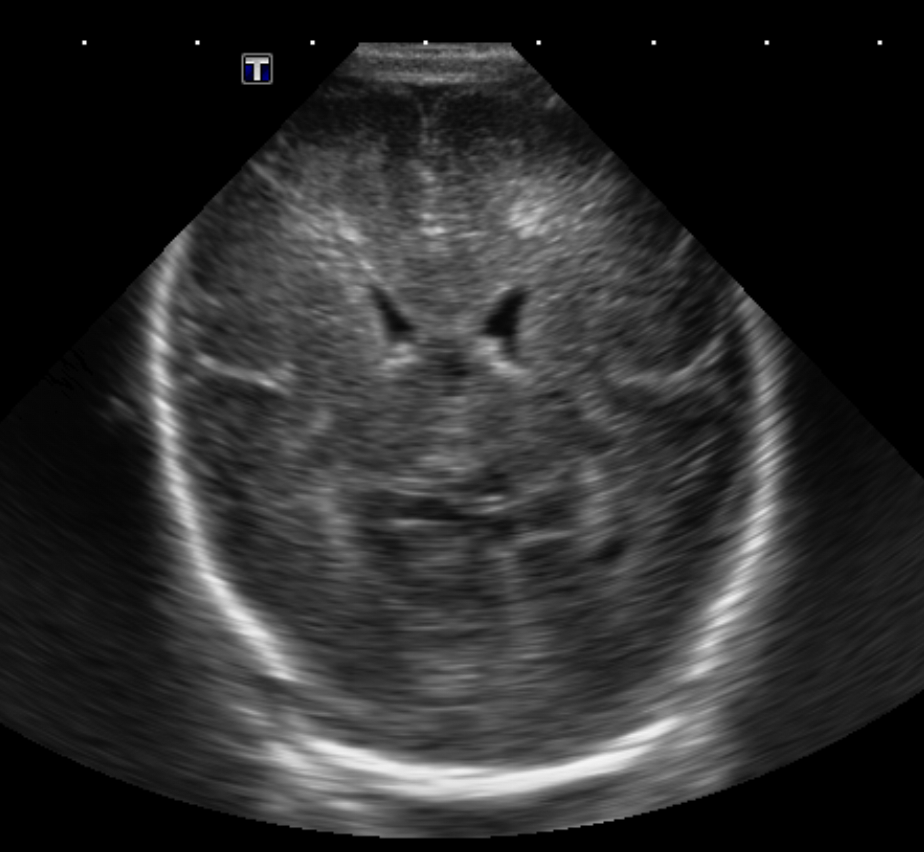

Info Images Findings Impression Reco/Acuity Case Images View Images / Launch Visage Case Notes History Full term infant. We are asked to evaluate posterior fossa cyst. Exam Gray scale and Doppler Ultrasonographic examination of the head. Prior Study N/A Dicom View Reference Material

Section 1 Submit Findings Case149 Findings Brain The brain is immature. Yes No There is under-sulcation and open sylvian fissures. Yes No There is/are multiple hypoechoic areas in the periventricular white matter. Yes No There is/are multiple hyperechoic areas in the periventricular white matter. Yes No There is diffuse cerebral edema with diffusely increased echogenicity of the brain parenchyma and loss of grey white matter differentiation. Yes No The thalami/basal ganglia are hypoechoic. Yes No There is periventricular calcification. Yes No There is intra-parenchymal calcification. Yes No CSF spaces/ventricular system There is a prominence of the extra axial fluid spaces. Yes No There are debris/septations in the extra axial fluid spaces. Yes No There are debris/septations in the ventricles. Yes No There is a subdural collection on the right/left side. Yes No There is prominence of the ventricular system. Yes No There is an asymmetry of the ventricular system. Yes No There is a cavum septum pellucidum. Yes No There is a midline shift towards right/left. Yes No The choroid plexus is bulky/lobulated. Yes No There is a choroid plexus cyst measuring… Yes No There are debris/clots in the occipital horn. Yes No There is a posterior fossa cyst measuring… Yes No The tentorium is elevated/depressed. Yes No The lateral ventricle/s are dilated. Yes No The third ventricle is dilated. Yes No The 4th ventricle is dilated. Yes No There are pseudo cysts. Yes No Germinal matrix hemorrhage (Only in the premature infants): Please do not answer if the patient is a full term. There is a germinal matrix hemorrhage, consistent with a grade I hemorrhage. Yes No There is an intraventricular extension consistent with a grade II hemorrhage. Yes No There is an intraventricular extension with the dilatation of ventricles, consistent with a grade III hemorrhage. Yes No There is an intra-parenchymal extension, consistent with grade IV hemorrhage. Yes No On color Doppler examination, the Resistive index in the anterior cerebral artery is… There is a loss of the diastolic flow on the Doppler exam. Yes No There is altered vascularity on Doppler imaging. Yes No There is an AVM in the region of… Yes No